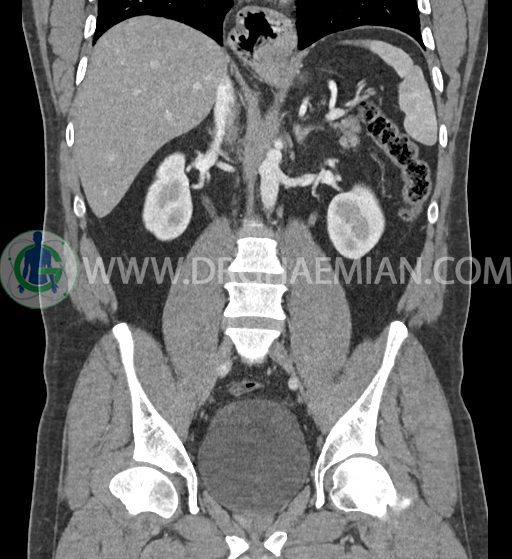

سی تی اسکن شکم و لگن با استفاده از اشعات ایکس تصاویر عرضی از ناحیه شکم و لگن ایجاد میکند. در این کیس فتق هیاتوس و هیدرویورترونفروز دیده می شود.

در سی تی اسکن اسپیرال شکم و لگن با کنتراست خوراکی و وریدی (مولتی دیدکتور 16 با مقاطع ظریف و بازسازی های ساژیتال و کرونال) :

کلیه ها کنتراست را ترشح کرده اند و نمای سیستم پیلوکالیسیل و حالب دو طرف نرمال است .

-هیدرویورترونفروز جزئی دو طرفه دیده می شود که می تواند ثانویه به اتساع مثانه باشد.